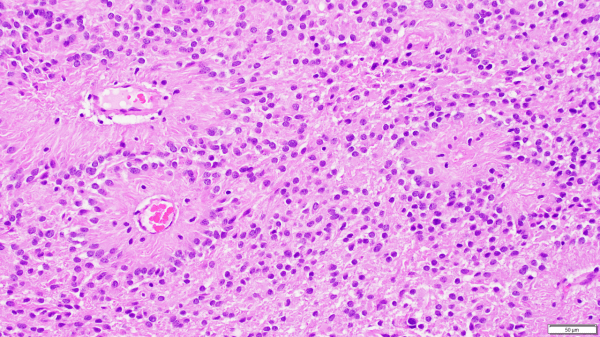

The microscopic appearance of ependymomas is dominated by the presence of radially-arranged tumor cells forming rosettes (black arrows), which are named for their resemblance to the flower-like architecture of rose windows in gothic cathedrals. The perivascular pseudorosette, characterized by tumor cells radially arranged around a central vessel, is more common by far, but it is not specific to... Continue Reading →

Ependymomas are glial tumors that commonly harbor perivascular pseudo-rosettes, seen here, characterized by radially arranged tumor cells around a blood vessel core. https://youtu.be/UXDIYV_yMro